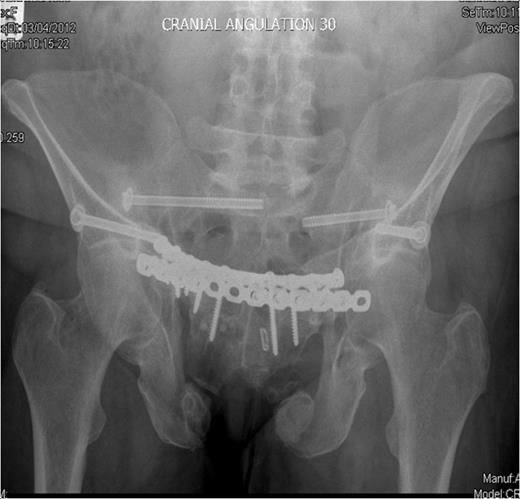

Following admission, routine blood parameters (including bone profile) were all normal and a pelvic MRI scan out-ruled any intra-pelvic soft tissue lesions. Open reduction and internal fixation of her anterior pelvic ring was undertaken through a Stoppa approach, both rami fractures were reduced and plated anteriorly and superiorly. At this time bone and soft tissue samples from the anterior ring were sent for analysis. Following reduction and fixation of her anterior pelvis, intra-operative fluoroscopy revealed that her posterior injuries were in an acceptable position. A 3cm long vertical incision was made over both anterior inferior iliac spines and supra-acetabular screws were placed from the anterior inferior iliac spines to the posterior inferior iliac spines to fix the bilateral iliac wing fractures. Finally bilateral percutaneous sacroiliac screws were inserted to stabilise the sacro-iliac joints.

Inlet radiograph at 16 months post surgery demonstrating solid fixation and bony healing

Post-operative recovery was uneventful. Bone and soft tissue biopsies showed no abnormalities. She was kept non weight bearing for 12 weeks. Subsequent dual energy X-ray absorptiometry scanning revealed mild osteopenia for which she is being managed medically. She began full weight bearing at 3 months post surgery. Final follow-up at 16 months demonstrated that the fractures had healed, and the patient was pain free and mobilising unaided (Fig. 3 & 4).

Outlet radiographs at 16 months post surgery demonstrating solid fixation and bony healing